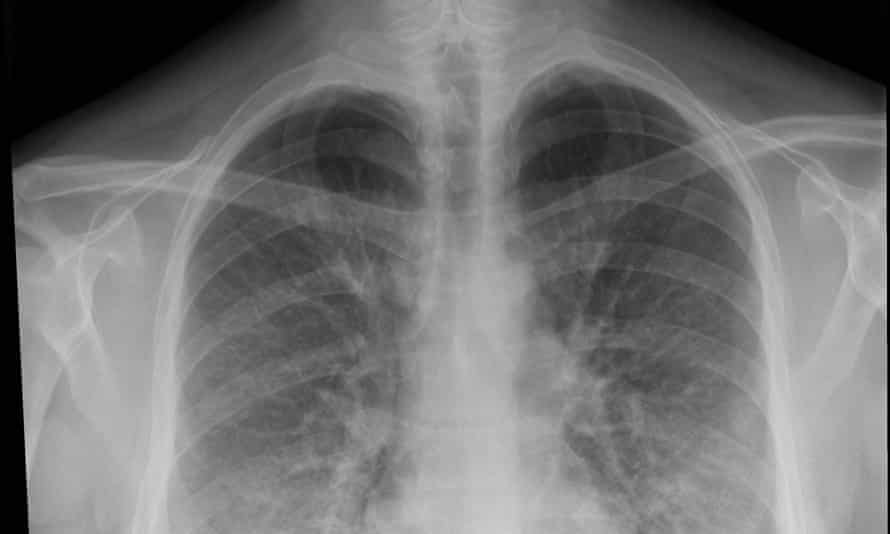

The air sacs of the lungs become inflamed and fill with fluid. The lungs of course are responsible for supplying oxygen all over the. If you stop you risk having the infection come back and you increase the chances that the germs will be resistant to treatment in the future.

Your risk for viral pneumonia is greater if you are older than 65 or you have lung or heart disease. It causes the air sacs in the lungs to become inflamed and to fill with pus and fluid. Plenty of fluids taken orally or intravenously antibiotics to kill the infection if bacteria are the cause medications to relieve pain and reduce fever.